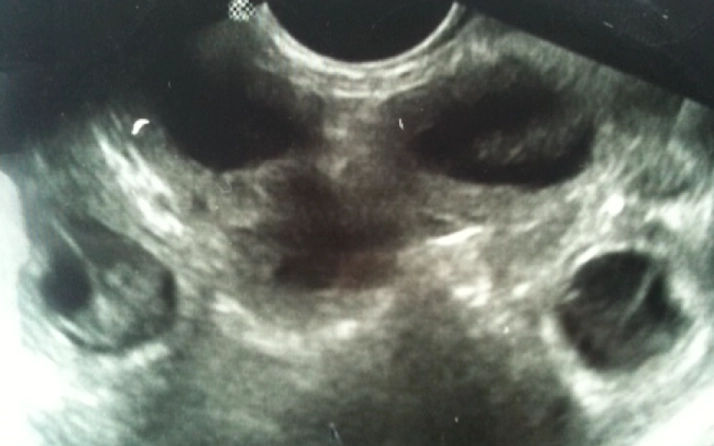

Medical ultrasound image showing internal structures.

This is a sonogram of Bitsy's pups. You can see 5 circles which are 5 different puppies. The one the bottom left is a good view of the pup in its sac. These pups are about 35 days old.